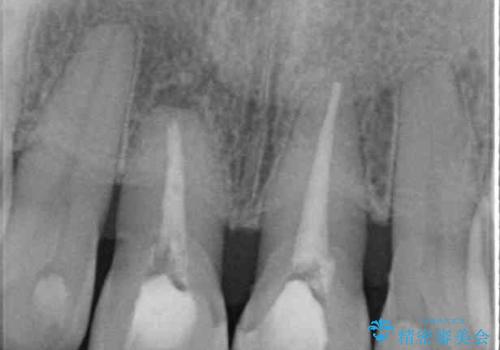

- 上の前歯の変色と、下の前歯のデコボコを気にして来院された患者様です。

前歯はオールセラミッククラウンに補綴することとしました。

補綴治療に先立ち、下顎前歯の部分矯正を行い、前歯の咬み合わせの安定性向上を図りました。

当初は上顎の補綴治療のみを希望されていましたが、奥歯にブリッジなど補綴物が多くあり、前歯も変色しているため、治療費が高額となってしまうことが懸念されました。